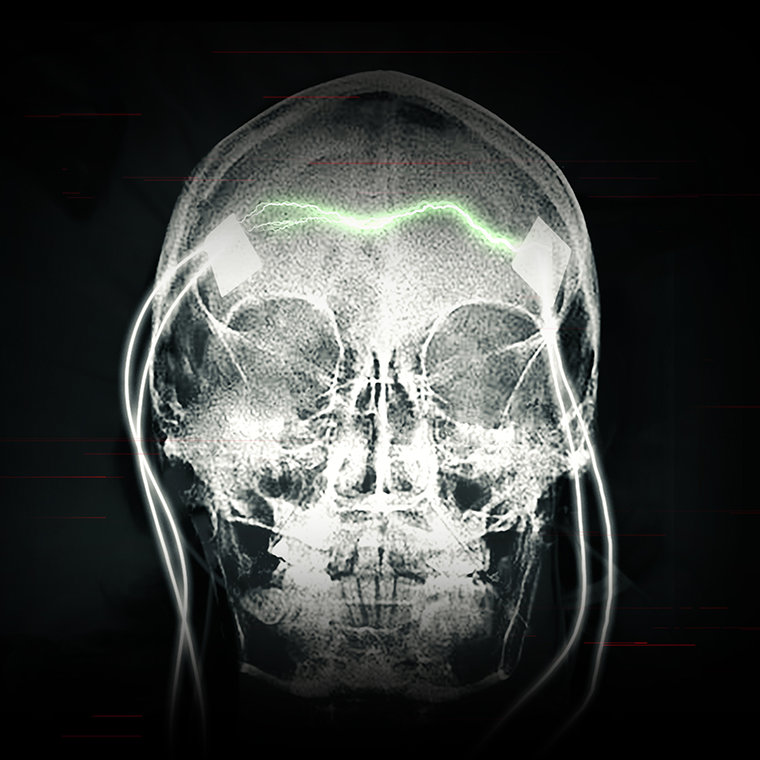

Результат остаётся прежним: большой судорожный припадок и повреждение мозга, которое может оказаться необратимым. Значительно больший ток, применяемый сегодня, может создать разрывы в клетках мозга, тем самым убивая их. Электричество также может убить клетки, нагревая их. Проведённая пациентам ЭСТ магнитно-резонансная томография (МРТ) показала: шрамы на мозге и его усыхание – неоспоримые доказательства тяжёлых повреждений.